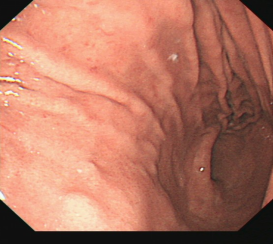

直肠巨大侧向发育型肿瘤,内镜下完整切除(ESD),术后病理证实粘膜内癌,不需追加治疗,达到治愈目的,保留正常器官,避免外科手术。